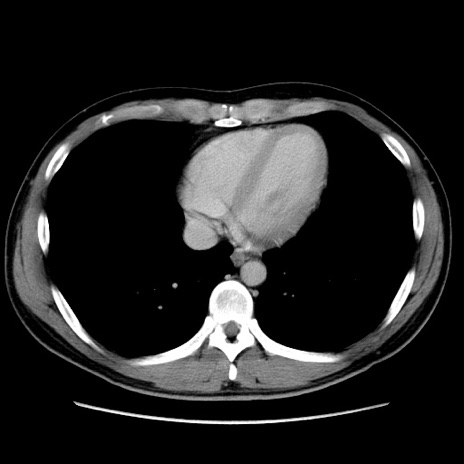

症例36(横断像)

【症例】20歳代 男性

【主訴】心窩部痛

【現病歴】今朝より上腹部痛あり。一旦軽快していたが再度出現したため救急要請。昨日夕に白身の魚を含む刺身を食べた。

【身体所見】BP 136/89mmHg、HR 74/min、BT 37.0℃、腹部:膨満、軟、心窩部に圧痛あり。反跳痛なし、筋性防御なし、腸雑音やや亢進あり。

【データ】WBC 17700、CRP 0.48